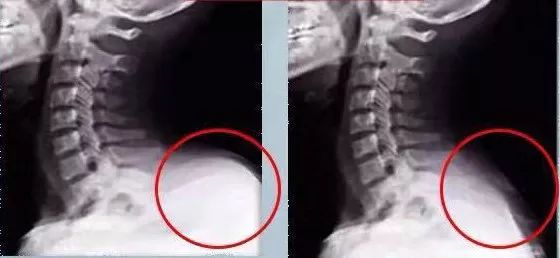

为了解释这个问题,我们来看看女孩的背部x光片.

在使用了一个多月苗王追风液之后,原本凸起的大椎穴,在x光下也可以